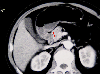

A case of a cystic tumor with septa which developed in the stomach.

CT

Histopathological Classifications

Non-epithelial tumors/Cyst